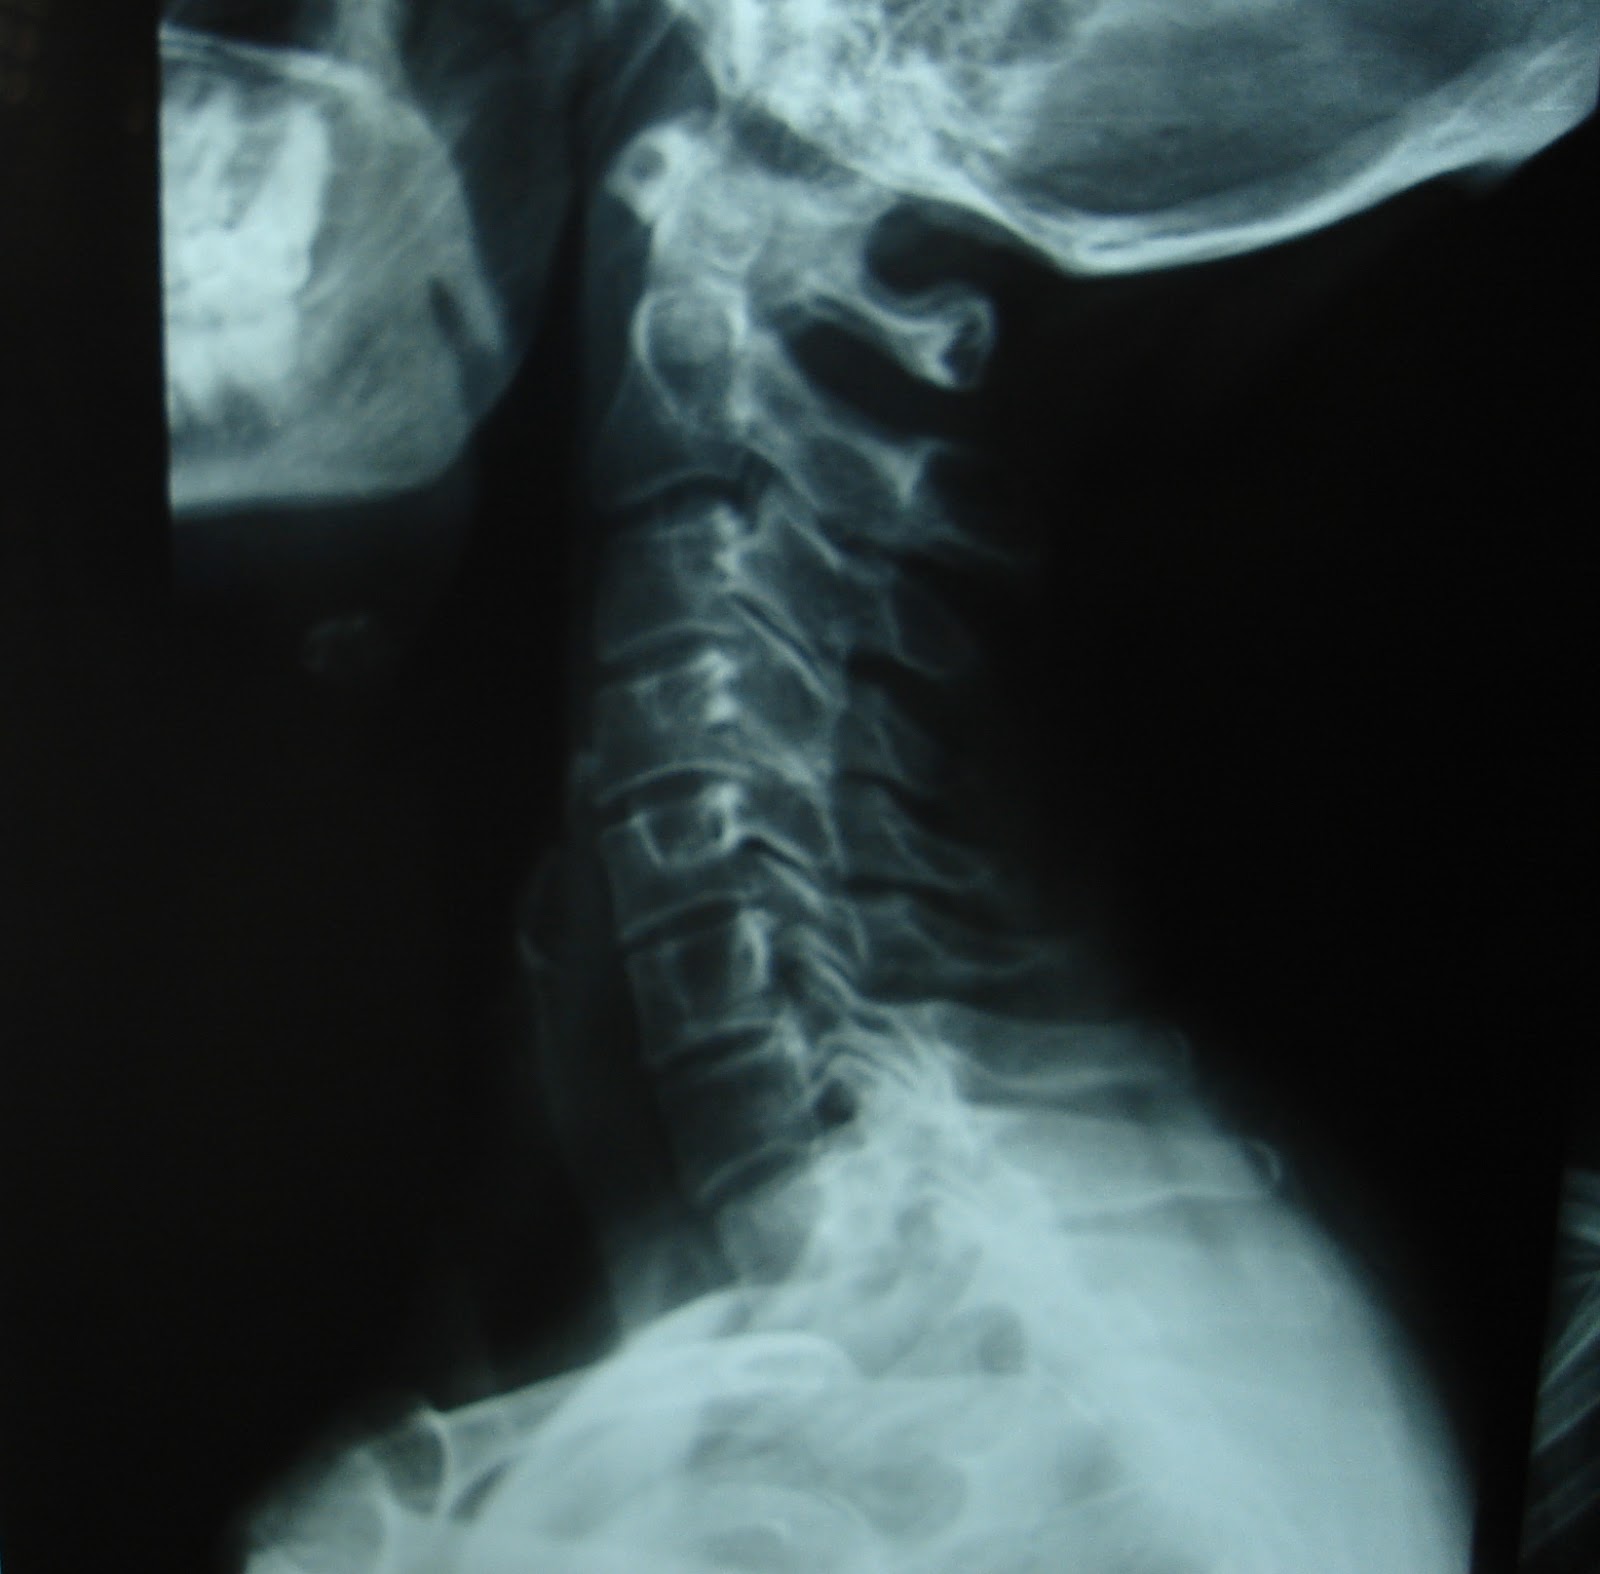

Rectificacion De Lordosis Cervical Fisiologica Como Minusvalia. WebLa rectificación de la lordosis cervical es el aplanamiento de esta curva. Las curvas de la columna no están de más, nada lo está en el cuerpo. Aumentan la protección de la.

WebLa rectificación cervical o rectificación de la lordosis cervical consiste en la pérdida de la lordosis fisiológica (curvatura natural) de esta región de la columna.. WebY el objetivo del tratamiento será reconstituir la lordosis fisiológica (curvatura normal) de la columna cervical. Hay tres pases obligatorios para trabajar una.

WebLa lordosis cervical es la curvatura normal de las cervicales. Es decir, en un estado «normal» todos tenemos lordosis cervical. Entendemos que tienes lordosis cervical. WebLa lordosis cervical es una curvatura anormal hacia adentro en el área del cuello que hace que la cabeza parezca estar empujando hacia adelante (o sobresaliendo) más allá de su. WebLa rectificación cervical, es una patología que se presenta cuando se pierde o disminuye considerablemente la curvatura normal o fisiológica de la columna cervical,.